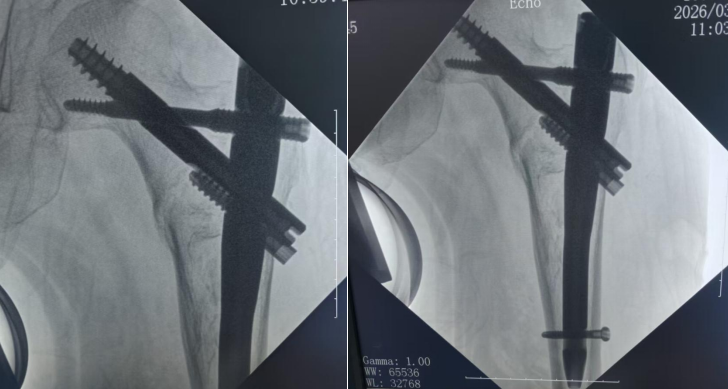

患者杨阿姨因在家中不慎跌倒致右髋部骨折,术后次日即可下床活动。考虑到患者年龄及快速恢复的实际需求,蔡青主任医师团队在张英泽院士团队远程指导下,经多学科联合会诊,为其量身定制了PFBN微创手术方案。术中在C臂透视精准定位下,成功置入PFBN仿生髓内钉及锁定螺钉,构建出符合人体骨骼生物力学的三角稳定结构。手术创伤小、出血少,术后患者生命体征平稳,疼痛显著缓解。

PFBN技术是由张英泽院士团队基于“张氏N三角理论”研发的新型骨科内固定技术,通过双三角立体稳定结构,改变了传统单一固定模式。相比传统手术方式,该技术在稳定性、微创性、把持力及术后恢复速度等方面均表现出明显优势,尤其适用于骨质疏松的老年患者,可有效减少因长期卧床引发的并发症风险。